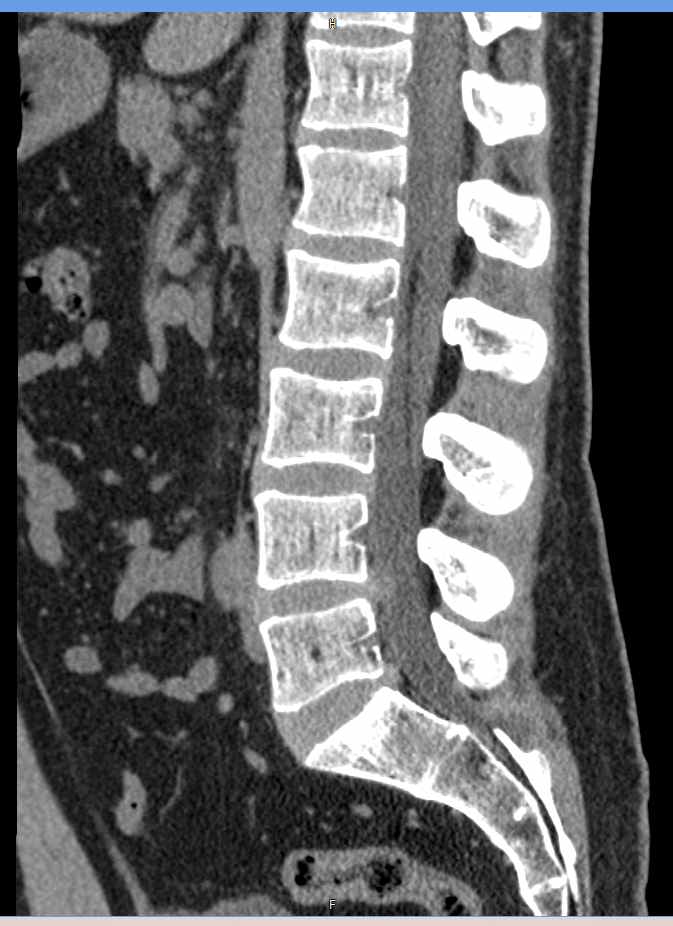

Мультиспиральная компьютерная томография является наиболее точным и информативным методом диагностики различных заболеваний позвоночника и, в частности, пояснично-крестцового отдела. Сканирование проводится при помощи рентгеновского излучения, в результате чего получают серию послойных изображений пояснично-крестцового отдела позвоночника.

В медицинских центрах «Доступная медицина» обследование пояснично-крестцового отдела позвоночника осуществляется на современных мультиспиральных компьютерных томографах последнего поколения TOSHIBA AQUILION в модификациях, позволяющих выполнять одномоментно 64 и 128 срезов анатомической зоны для получения снимков высокого разрешения. Послойное сканирование исследуемой области проводится с минимальной толщиной среза от 0,5 мм, что обеспечивает получение изображений органов в мельчайших подробностях.

Инновационные компьютерные приложения позволяют построить 3D-модель исследуемого органа, обеспечивая детальную визуализацию строения внутренних структур позвонков, хрящевых элементов, кровеносных сосудов и окружающих тканей.

На КТ пояснично-крестцового отдела позвоночника врач может оценить

- состояние дугоотростчатых сочленений;

- изгиб позвоночного столба (поясничный лордоз нормальный, усилен или сглажен);

- не смещены ли позвонки относительно друг друга;

- нет ли признаков костной деструкции, остеопороза;

- нормальная ли высота тел позвонков;

- нет ли грыж (протрузий, экструзий), и если есть – где они находятся, на сколько миллиметров выступают в просвет позвоночного канала, какие анатомические структуры сдавливают;

- состояние паравертебральных мягких тканей (возле позвоночника).